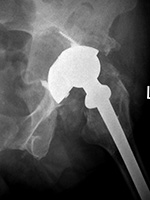

Metal-on-metal left hip arthroplasty with metallosis and bony erosions |

68 year-old woman with left hip metal-on-metal prosthesis. Bony erosions (arrows) are evident on the greater and lesser trochanters from probable metallosis with pseudotumor formation. |